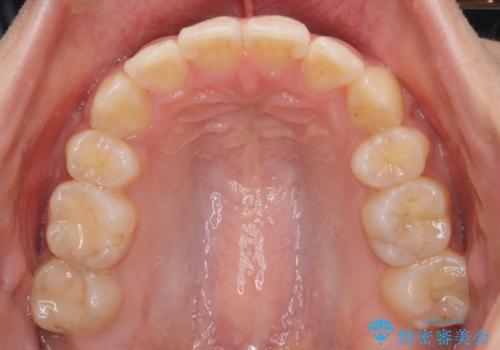

- 八重歯を主訴に来院されました。4番の歯を4本抜歯し、八重歯を並べる計画をたてました。

抜歯をし、スペースを確保したことにより八重歯をきれいに並べることが出来ました。